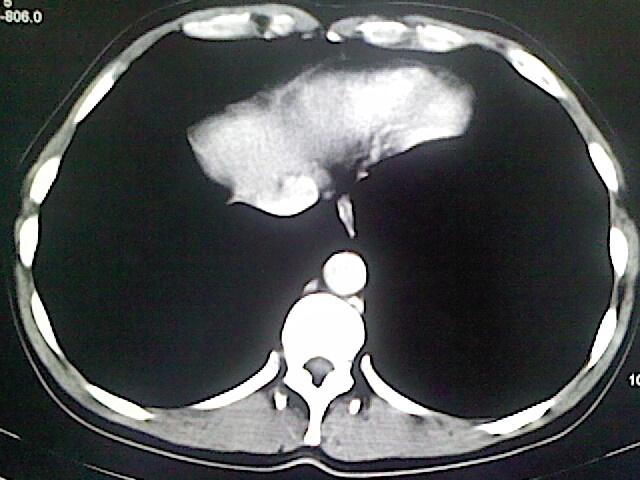

以下是引用卜一在2009-3-14 9:49:00的发言:[br]胆囊萎缩,胆囊壁不规则增厚,内部结构模糊,增强明显强化。另:肝左叶外侧段肝囊肿。支持:慢性胆囊炎!高度可疑:胆囊癌!

以下是引用余辉在2009-3-14 8:48:00的发言:[br]1)慢性胆囊炎。2)肝左叶外侧段肝囊肿。3)脂肪肝。[br]支持,胆囊萎缩,密度增高,不知b超具体有何提示,钙胆汁?结石?

以下是引用jiangjing在2009-3-14 10:18:00的发言:[br]1)慢性胆囊炎。2)肝左叶外侧段肝囊肿。3)脂肪肝。4.】建议行肝功能检查